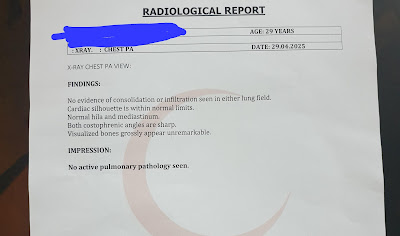

PaJR PHR Moderator: If it's truly musculoskeletal then one need not worry. A chest X-ray image could tell us further.

PaJR PHR Moderator: Thanks! The lungs look hyperinflated. Did she ever have any history of bronchial asthma?

29F IBS: No sir. No history of bronchial asthma.

When she was going through mental health issues in 2019. She had severe breathing issues. She used to breath though mouth. Later with years it got better.

In 2020 allergy got triggered she sneezed non stop for a month. Till this date with perfume, dust, smoke or any unknown things triggered the allergy every week where she either get better on its own within an hour or she has to take cetrizine/levocetrizine.

Still with just few physical work or stressed she has breathlessness.

PaJR PHR Moderator: These symptoms are matching her chest X-ray